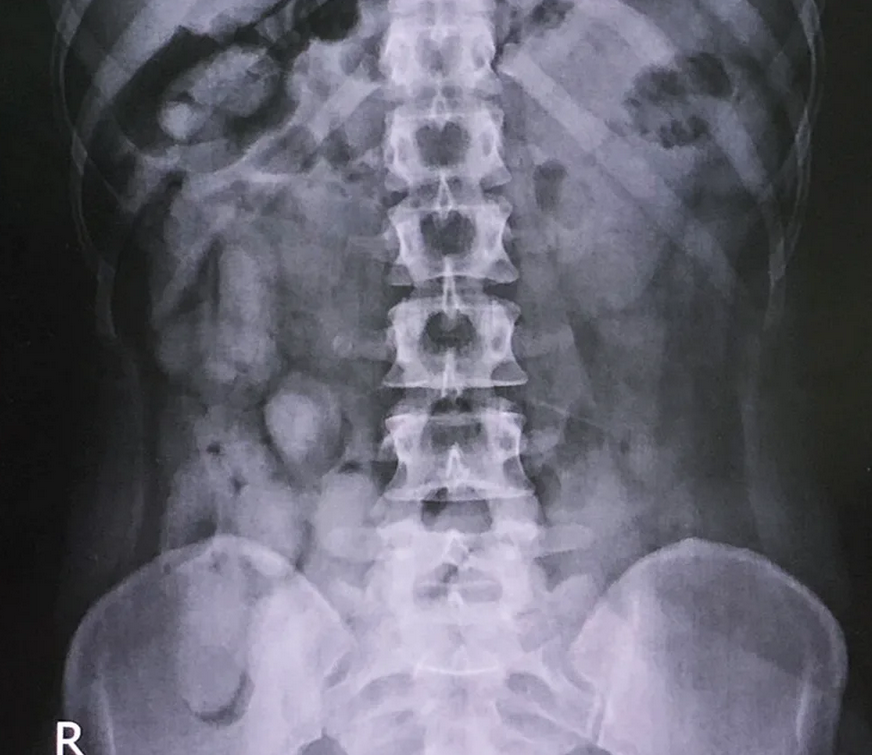

Anfangs schien alles unauffällig zu sein, als die Frauen auf dem Flughafen angehalten und durchsucht wurden. Doch erst Röntgenaufnahmen in einem nahegelegenen Krankenhaus enthüllten das erschreckende Geheimnis: Die Frauen hatten Kokainbehälter in ihren Vaginas versteckt und Kokainbündel verschluckt.